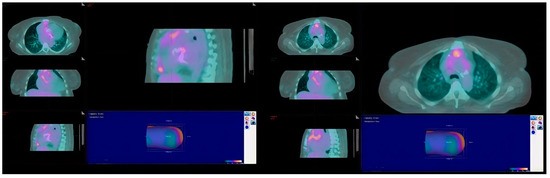

2. Case Presentation